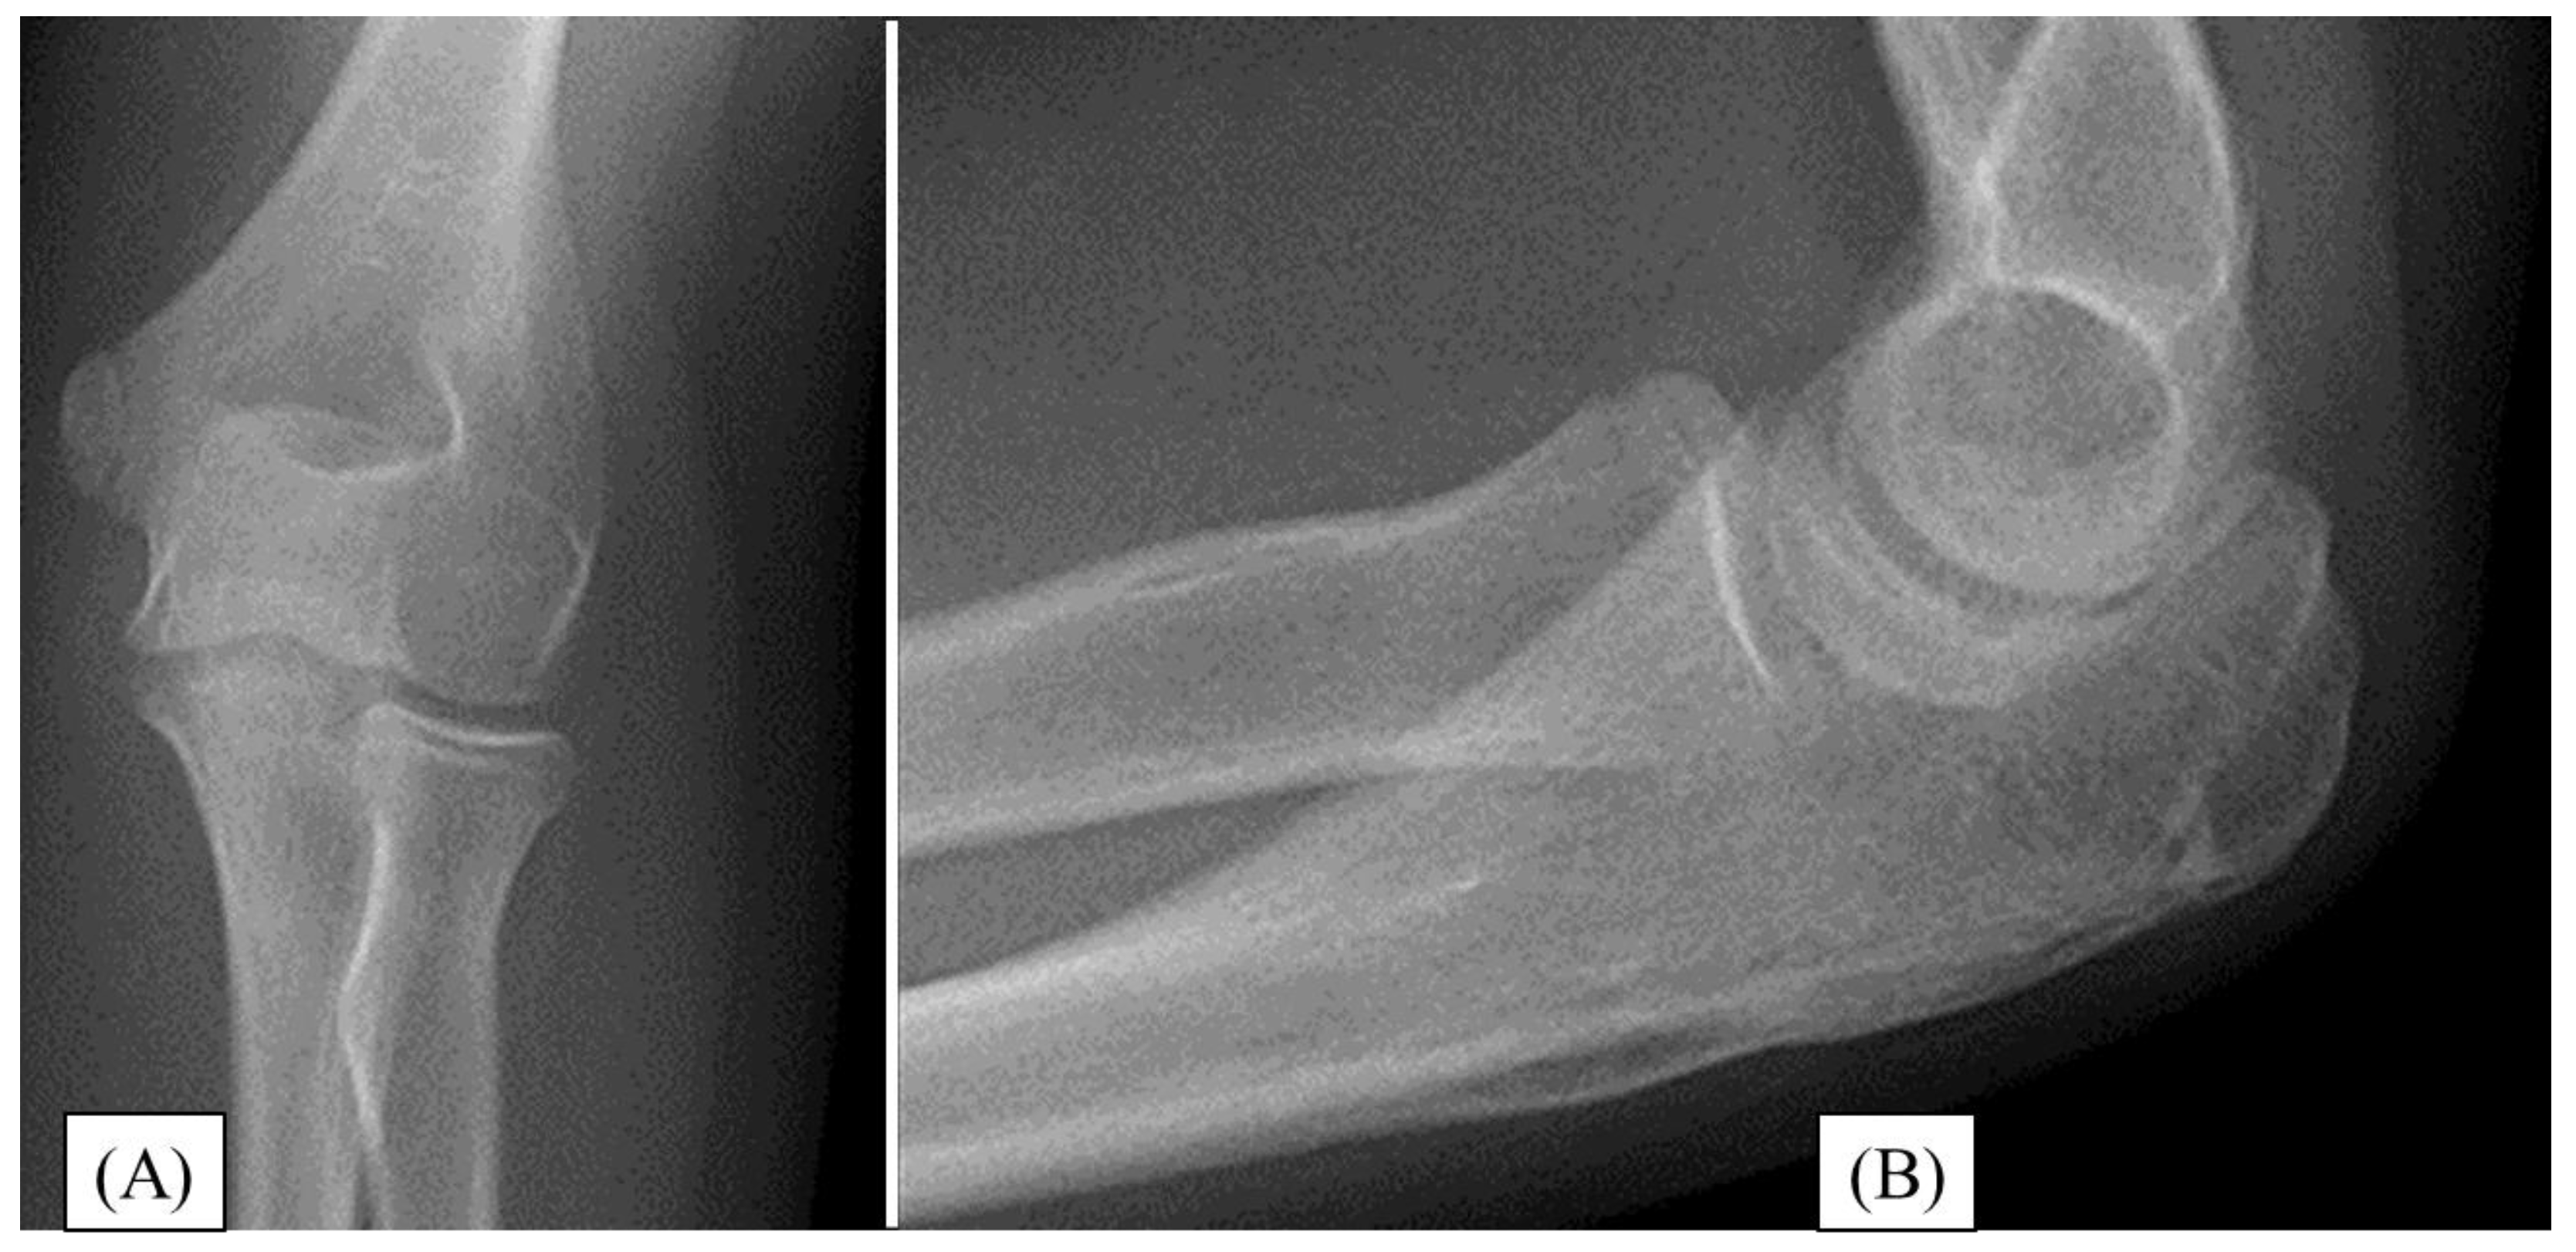

3.3. Case 3

A 13-year-old boy injured his right elbow while cycling. He presented with significant swelling and restricted ROM. X-rays confirmed a comminuted Mayo type II/A olecranon fracture with joint involvement (Figure 4A,B). During open surgery, after achieving the most accurate reduction, the fracture was stabilized with absorbable implants (PLGA pins and a PDS loop) (Figure 4C,D). The postoperative period proceeded without complications. After three weeks of casting, the child underwent active physiotherapy. During follow-up, healing of the fracture was observed. One-year follow-up showed complete healing of the fracture on X-ray (Figure 4E,F), with full elbow joint function.

Figure 4. Initial X-rays of the right olecranon fracture (AP (A), lateral(B)), and the postoperative radiographs show acceptable articular congruency (AP(C), lateral (D)). One year later the X-ray images (AP (E), lateral (F)) depict good alignment and perfect articular congruency.